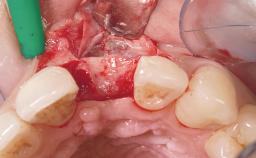

A 42-year-old female patient was referred to our clinic at the School of Dentistry of the University of São Paulo in November 2004, presenting a deficient restoration in the upper left central incisor. The clinical examination revealed no gingival retraction or any signs of gingival inflammation and, therefore, previous periodontal treatment was not considered. The patient presented a high lip line at full smile and a thin tissue biotype. This combination characterized a high-risk situation from an anatomic point of view, which required careful preoperative planning and cautious surgical execution.